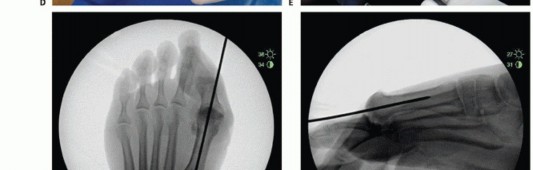

- TECH FIG 1 • Guide pin placement. A. Intraoperative picture of spherical guide placement just above the crista of the first metatarsal. B. AP view of pin placed in line with the long axis of the first MTP shaft. C. Lateral image of pin placed parallel to the long axis of the MTP shaft. The surgeon can drop his or her hand as necessary to match the inclination of metatarsal and midline within the shaft. (continued)

The perimeter of the guide should not violate the metatarsosesamoid complex and its inferior border is

generally seated just above the crista. Avoid malplacement of the guide pin by plantarflexing the guide as necessary to adjust for normal inclination of the metatarsal shaft. It is critical that this be in line with the long axis of the metatarsal shaft on the lateral fluoroscopic view.

Place the centering guide pin on the metatarsal head in line with the long axis of the metatarsal shaft and verify its position on AP and lateral fluoroscopic views. Adjust the guide pin as necessary to obtain correct placement (TECH FIG 1A-E). Pay particular attention to the guide pin lateral view, for there is a tendency to underestimate the degree of inclination of the metatarsal shaft; parallel to the long axis of the shaft is the desired position. Adjust the pin before proceeding.